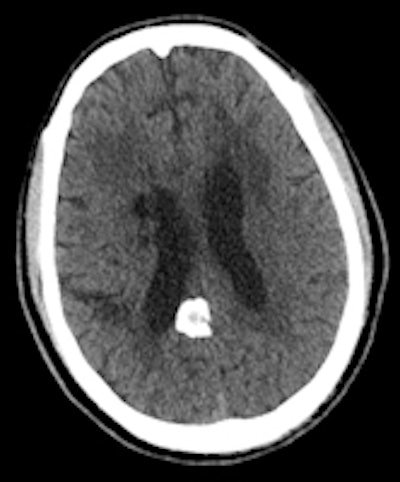

A 60-year-old man known to have HIV presented with seizures. The solid calcifications on noncontrast enhanced CT (NCECT) at the right frontal (left), left basal ganglia (middle), and right parietal areas (right) represent sequela following treatment for documented toxoplasmosis. All images courtesy of Dr. Froilan Celzo.

Same patient: Coronal (left) and sagittal (right) 3D reconstructions are shown.Also known as cerebral calculi, brain stones may be extra- or intra-axial in location. Extra-axial brain stones comprise tumors and exaggerated physiological calcifications, while intra-axial calcifications can be classified under neoplastic, vascular, infectious, congenital, and endocrine/metabolic etiologies, they wrotein an article published online on 11 September by Insights into Imaging.

The dense calcifications seen in patients with congenital toxoplasmosis can also have a random distribution, with lesion sizes that correlate with the duration of infection. Treatment can result in shrinkage and even resolution of these calcifications (see figure).